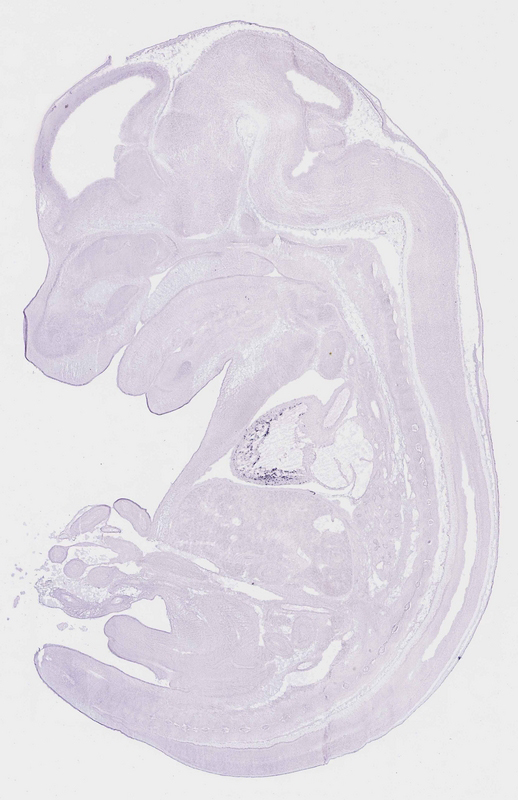

Reference: J:153498 Diez-Roux G, et al., A high-resolution anatomical atlas of the transcriptome in the mouse embryo. PLoS Biol. 2011;9(1):e1000582

Assay type: RNA in situ

Gene symbol: Nppb

Gene name: natriuretic peptide type B

Specimen euxassay_002897_08: embryonic day 14.5 (more )

TS23: heart ventricle Strong Single cells euxassay_002897_08